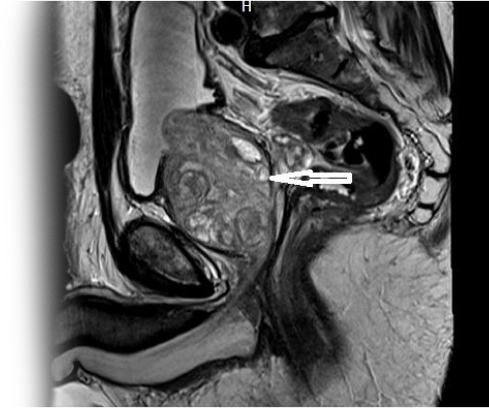

Магнитно-резонансная томография органов малого таза с контрастированием – важный метод исследования с введением контрастного вещества, который позволяет визуализировать предстательную железу, семенные пузырьки, мочевой пузырь и прямую кишку.

Как проводится МРТ органов малого таза с контрастом?